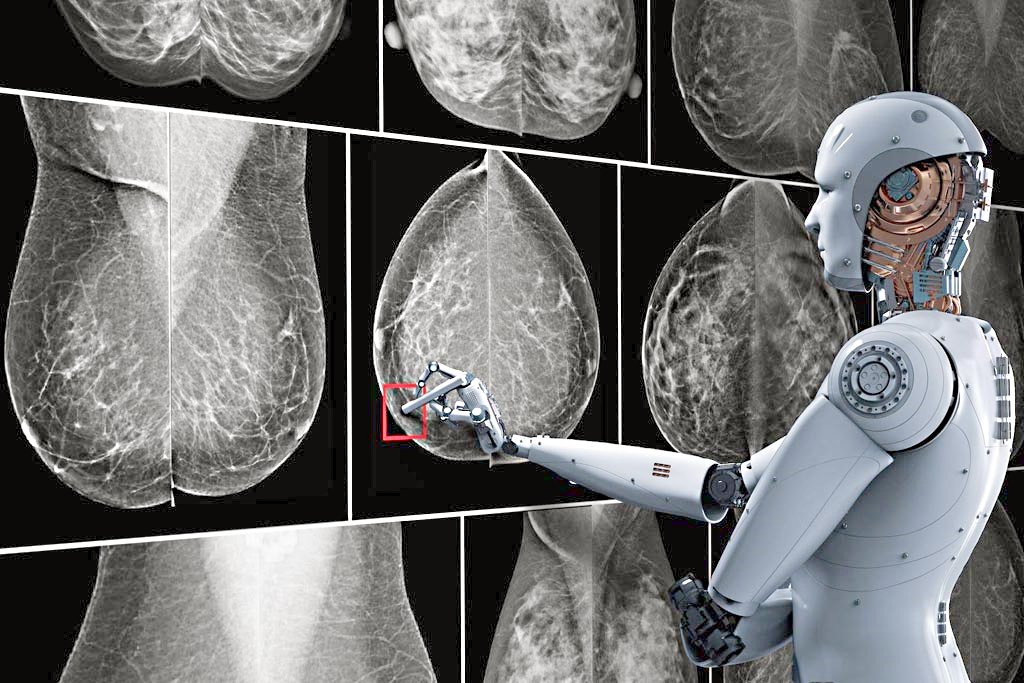

الذكاء الاصطناعي يتنبأ بسرطان الثدي قبل 5 سنوات من ظهوره… بدقة غير مسبوقة

ازيح الستار عن تقنية جديدة تعمل بالذكاء الاصطناعي تقوم بتحليل صور الماموغرام، إلى جانب عمر المريضة، لتقدير احتمال إصابتها بسرطان الثدي خلال الخمس سنوات القادمة. ويعمل هذا النظام مع الصور الثنائية الأبعاد التقليدية وصور التصوير المقطعي ثلاثي الأبعاد للثدي، ما يجعله قابلًا للتطبيق على أنواع الفحص المعتمدة في العيادات والمستشفيات. كما يوفّر النظام نسبة مئوية دقيقة تمثل درجة خطر الإصابة، ما يمكّن الأطباء من مقارنة مستوى الخطر لدى المريضة بالمعدل الوطني العام.

أظهرت النتائج أن هذه التقنية القائمة على الذكاء الاصطناعي تحقق دقة تصل إلى أكثر من ضعف دقة الطرق التقليدية التي تعتمد فقط على استبيانات لعوامل الخطر مثل العمر والوراثة والتاريخ العائلي. وقد تم تدريب الخوارزمية على صور لمئات الآلاف من الحالات، ما مكّنها من التعرّف على مؤشرات دقيقة للغاية للسرطان، لا يمكن ملاحظتها بالعين المجردة. وبما أن البنية التحتية لفحص الماموغرام موجودة بالفعل في معظم المستشفيات، فمن السهل دمج هذه التقنية في الإجراءات الصحية المعتمدة دون الحاجة لاستثمارات جديدة.